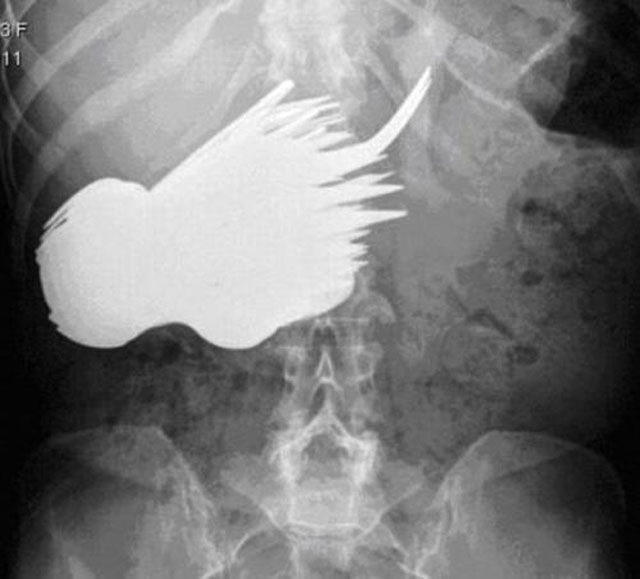

This incident was not an accident, it was intentional. The late Ryan Dunn of the television show Jackass intentionally inserted a Matchbox car into his rectum just to mess with the ER doctors.